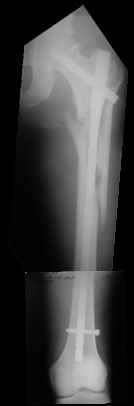

I would prefer Gamma because of its features preventing migration of the neck screw.

I would use a small wire distractor mentioned in the list some times. Proximal wire is in the iliac crest in AP direction. The leg is adducted. I attached some images. At the AP view under image intensifier you can see adduction but even slight valgus reduction.